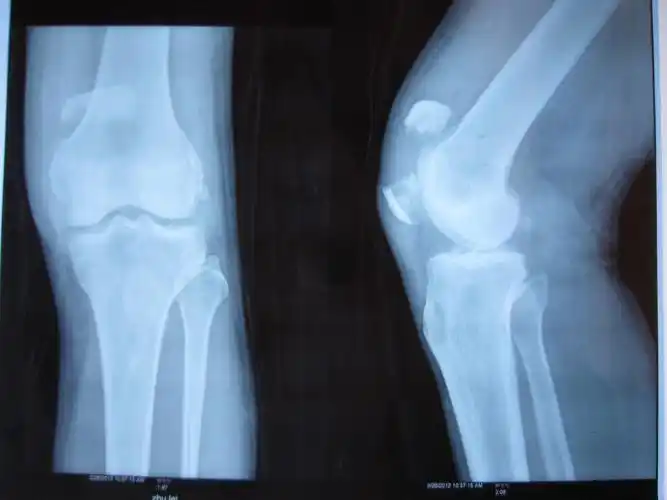

征集髌骨骨折x光片按要求提供给予积分